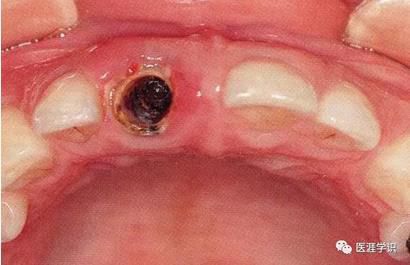

[拔牙造成的牙槽嵴凹陷]

▲圖1-1

右上1拔牙前狀態(tài)。

▲圖1-2

右上1拔牙后2個(gè)月的狀態(tài)。唇側(cè)骨板較薄時(shí),

在拔牙后的牙槽骨吸收會(huì)很明顯。

▲圖1-3

在拔牙時(shí)如果不小心破壞了唇側(cè)牙槽骨的話(huà),血塊就無(wú)法從唇側(cè)滲透,在拔牙窩形成凹陷部,造成的結(jié)果就是修復(fù)體的橋體部分發(fā)生美觀問(wèn)題。